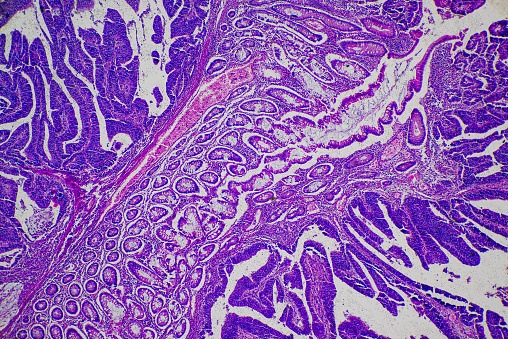

The researchers began by conducting a single-cell RNA analysis of a small sample of tissue, such as a cancerous tumor. From there, they separate the cells in the tumor and observe the RNA that each cell produces. This process creates a “bar code,” a pattern of RNA expression that identifies not only what kind of cell is being examined, but also the subtype of mode the cell is operating within. The researchers then analyzed over 1,000 whole tumors using the technique and discovered not only differences between cancer cells and normal cells, but also found that immune cells infiltrating a tumor behaved differently than circulating immune cells. Moreover, their research suggests that even normal structural cells encircling the cancer cells acted differently than the same type of cells in other parts of the same organ.